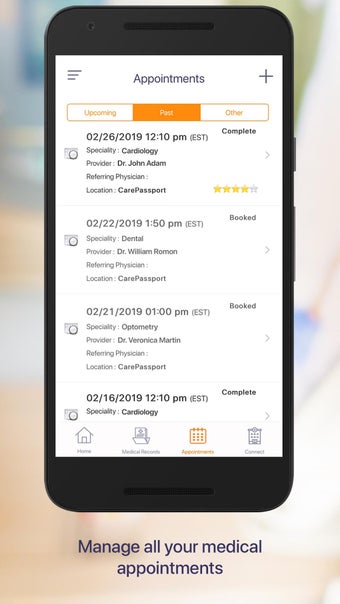

Carepassport là một ứng dụng Android cung cấp cho bệnh nhân một giải pháp toàn diện để quản lý dữ liệu y tế của họ. Ứng dụng cho phép bệnh nhân truy cập và lưu trữ an toàn dữ liệu y tế của mình, lên lịch hẹn, xem hình ảnh y tế, báo cáo xét nghiệm và lâm sàng từ các nhà cung cấp khác nhau, và chia sẻ chúng bằng công nghệ tính toán di động tiên tiến. Với Carepassport, bệnh nhân có thể dễ dàng quản lý nhu cầu chăm sóc sức khỏe của mình chỉ với vài lần chạm trên thiết bị di động của họ.

Một trong những tính năng quan trọng nhất của ứng dụng là việc truy cập dữ liệu y tế một chạm dễ dàng. Bệnh nhân có thể truy cập dữ liệu y tế của mình hoặc dữ liệu đại diện gia đình một cách an toàn và nhanh chóng, làm cho nó trở thành một công cụ tuyệt vời để quản lý lịch sử bệnh án của họ. Ứng dụng cũng cho phép người dùng tìm kiếm các phòng khám và bệnh viện gần đó, lên lịch hẹn, và thậm chí nhận chỉ đường đến cuộc hẹn của họ qua Uber. Ngoài ra, bệnh nhân có thể giao tiếp với nhà cung cấp chăm sóc của họ qua tin nhắn an toàn, chia sẻ hình ảnh y tế và cho phép thành viên gia đình truy cập dữ liệu y tế của họ thông qua cài đặt proxy an toàn. Cuối cùng, ứng dụng cung cấp tài liệu giáo dục liên quan đến chăm sóc sức khỏe và có thể kết nối với các thiết bị đeo được hoặc nhập dữ liệu y tế thủ công.